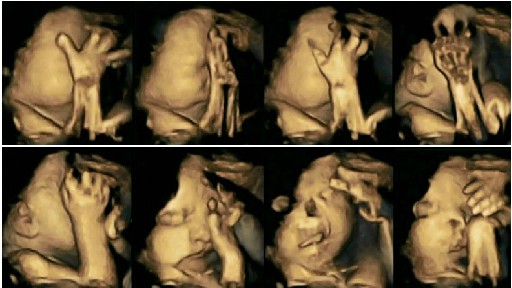

In imaginile de mai sus a fost suprins fatul unei mame care nu fumeaza. In imaginea din interiorul articolului se vede diferenta socanta cu un fat de aproximativ aceeasi varsta dar cu o mama fumatoare.

Rezultatele unui studiu recent arata ca mamele care fumeaza in timpul sarcinii transmit fatului substantele nocive din tigari. Acest lucru il face pe fat sa isi miste gura si sa se atinga de mai multe ori decat copiii nenascuti ai mamelor nefumatoare.

La acest studiu au participa 20 de viitoare mamici. 4 dintre femei fumau cel putin o tigara pe zi. Imaginile surprinse cu o camera 4D arata pana si cele mai mici miscari ale fatului.